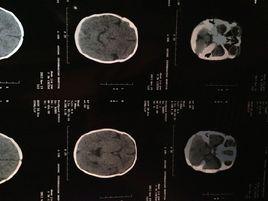

腦CT的正常值

1.檢查速度快,對新鮮出血敏感性高,並能顯示水腫及顱內壓增高,繼發腦疝等重要病變;腦CT也適宜診斷頭顱骨折,尤其是凹陷骨折和顱底骨折。

2.腦CT對腦血管疾病診斷準確,並有助於確定治療方案。

3.腦CT對顱腦損傷可分辨血腫的大小、形態、範圍、數目及其鄰近腦組織壓迫情況。觀察有無亞急性或慢性顱內血腫的存在,判斷顱腦損傷的吸收、縮小情況,亦可顯示腦軟化、腦萎縮、腦積水及腦穿通畸形等後遺症。

腦CT的臨床意義